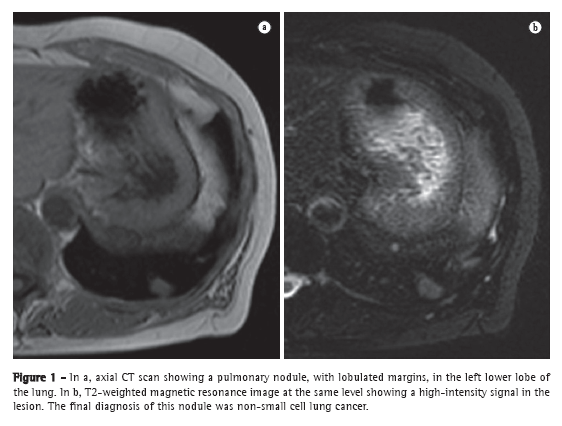

It is estimated that, in the United States, there are approximately 150,000 new cases of pulmonary nodules seen on routine chest X-rays every year.(9) One recent meta-analysis reported that dynamic CT and MRI, both of which are noninvasive methods, are equally accurate in distinguishing between malignant and benign solitary pulmonary nodules, the differences between the two tests being insignificant.(10) The authors of that meta-analysis found that, for the 10 dynamic CT studies, MRI had a pooled sensitivity of 93% (95% CI: 0.88-0.97) and a pooled specificity of 76% (95% CI: 0.68-0.97).(10) Koyama et al.(11) reported that non-contrast-enhanced MRI of the lung is as efficient as is thin-section multidetector CT in detecting malignant nodules. The authors also found that the overall nodule detection rate in each MRI sequence (82.5%) was significantly lower than was that of multidetector CT (97.0%), although there was no significant difference between the two techniques in terms of the detection rate for malignant nodules.(11) Figure 1 shows a comparison of images obtained with those two modalities.